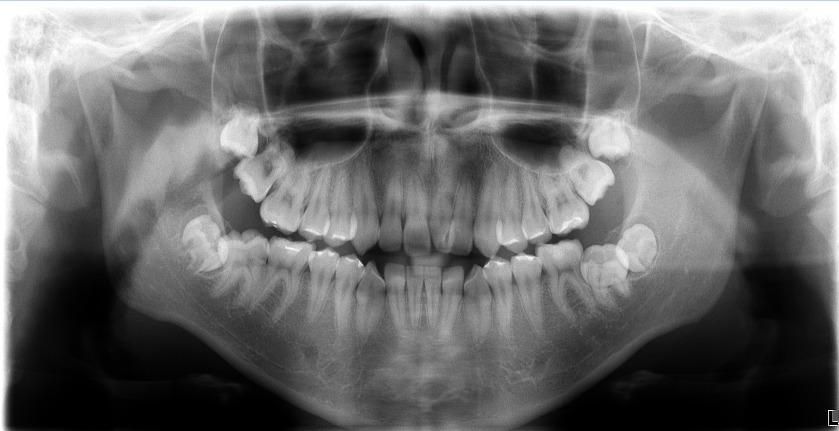

잇몸이 불편합니다. 엑스레이 봐주세요

1달 전에 오른쪽 아랫어금니쪽 잇몸이 부은 것 같아서 치과에 가니 엑스레이찍고 이것저것 체크해보더니 크게 이상있는 건 없다고 했어요. 그런데 며칠전부터 왼쪽 아래 잇몸이 불편합니다

엑스레이상에 보이는 게 있을까요?

사진상으로 오른쪽 아래 어금이 맹출방향이 약간 문제가 잇어서 잇몸관리가 안되는거 같습니다. 전체적으로 스켈링 및 잇몸치료를 먼저 받아보세요.

잇몸이 차례로 부은 것은 아마도 사랑니 때문일 것 같습니다. 사랑니가 맹출중이고요 잇몸을 건드리면서 불편을 야기할 수도 있습니다

추가적으로 왼쪽 아래 두번째 큰 어금니도 맹출방향이 바르지 않습니다 이와 관련하여 공간이 부족하지는 않는지 상담 받아보시면 좋을 것 같습니다